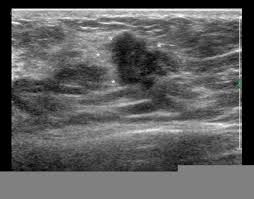

Inflammatory breast cancer, also known as carcinomatous mastitis, t4d, or pev 2 or 3, is the only real therapeutic emergency in breast oncology, given the high risk of metastasis, the reason for the most unfavourable prognosis of all breast cancers.it must consequently be diagnosed rapidly, and imaging examinations must in no case delay therapeutic management. The peak age at presentation may be comparatively younger than with other types of breast cancer 7. Ultrasound is not used on its own as a screening test for breast cancer. They're often easy to move around (mobile) and may be tender. Ultrasound may be particularly useful in detecting abnormalities in patients with dense breasts.

Ultrasound may be particularly useful in detecting abnormalities in patients with dense breasts. Finding breast lumps and seeing change in the size and shape. Ultrasound does not use or. Women or men who develop any of the inflammatory breast cancer early signs should seek medical care immediately to ensure timely treatment. The sound waves pass through the breast and bounce back or echo from various tissues to form a picture of the internal structures of the breast.

Computer Aided Assessment Of Tumor Grade For Breast Cancer In Ultrasound Images from static-01.hindawi.com Density is a term used to describe breast tissue that has many glands close together. Epidemiology these account for ~1% of breast cancers. Looks larger, thicker or heavier. That said, ultrasound is an extremely fast and powerful tool. Ibc is a rapidly progressive, aggressive form of breast cancer associated with a low overall survival rate. Is tender, aches or feels painful. Finding breast lumps and seeing change in the size and shape. Tubular carcinoma of the breast is a subtype of invasive ductal carcinoma (idc).